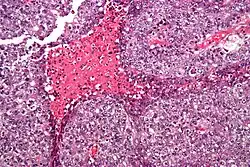

Micrograph of an embryonal carcinoma showing its typical features – prominent nucleoli, marked nuclear atypia, necrosis, and nuclear overlap. H&E stain.

The gross examination usually shows a two to three centimetre pale grey, poorly defined tumour with associated haemorrhage and necrosis.[3]

The microscopic features include: indistinct cell borders, mitoses, a variable architecture (tubulopapillary, glandular, solid, embryoid bodies – ball of cells surrounded by empty space on three sides), nuclear overlap, and necrosis.